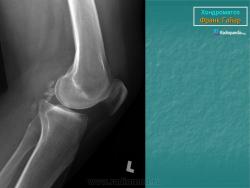

Хондроматоз суставов — хрящевая островковая метаплазия синовиальной оболочки

Хондроматоз суставов, или хрящевая островковая метаплазия синовиальной оболочки суставов, — сравнительно редкое заболевание. Впервые оперативное удаление внутрисуставного тела из коленного сустава было произведено Ambrois Pare в 1558 г. Первые описания хондроматоза суставов представили Пехлин [Pechlin, 1691], А.Монро [Мопго А., 1726], Д.Б.Морганьи [Morgagni D.B., 1761]. Однако только Р.Лаеннек (R.Laennec) в 1813 г. впервые указал, что внутрисуставные тела могут происходить из синовиальной оболочки. Описание хондроматоза суставов мы находим в руководстве по частной патологической анатомии К.Ракитанского, напечатанном на русском языке в 1847 г., в котором подробно описывается развитие хрящевых тел в синовиальной оболочке суставов. Наиболее известны работы B.C.B.Brodie (1836, 1850), Reiney (1848), A.Kolliker (1850), R.Virchov (1863) и др. Однако недостаточное знание литературы послужило причиной того, что в начале XX в. многие считали P.Reichel (1900) первым автором, описавшим «новое не известное до этого заболевание» — хондроматоз суставов, или даже считали его заболеванием Гендерсона—Джонса, описавших хондроматоз суставов в 1917—1918 гг.